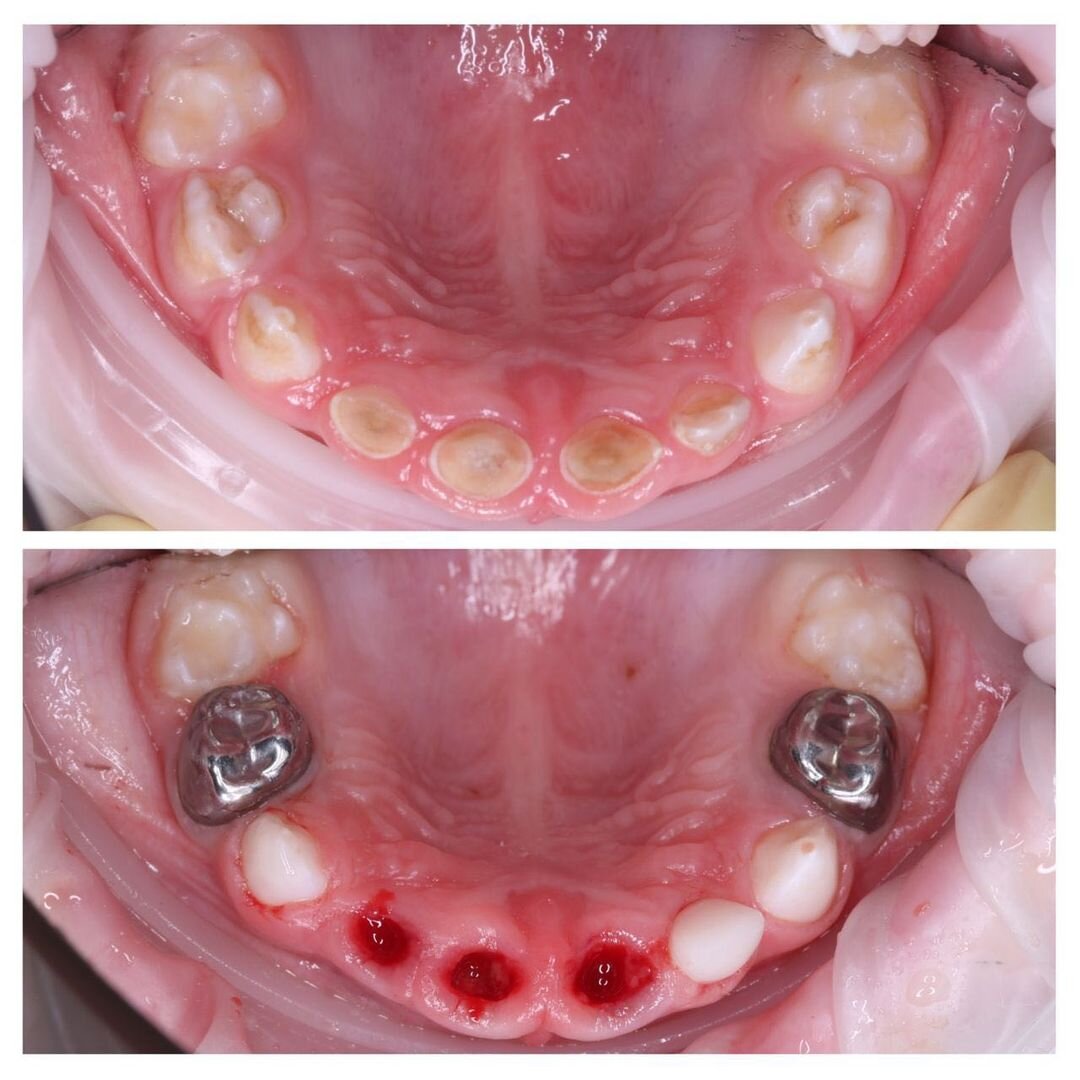

Не напугать ради, а мотивировать для…Удивительно, но именно такие фото мотивируют заботиться о здоровье зубов больше всего. В моем блоге их уже не пересчитать! Зубки молочные. Тают просто как масло на жаре. А двухлетний малыш не подпускает родителей с зубной щеткой в руках. Семья живет на Сахалине. Далеко, но как есть.. Помеха ли расстояние для лечения? Думаю, даже те, кто так считали ранее, пересмотрят свои взгляды. Вернемся к тому, что сделано. Прием вела детский стоматолог Мария Штельмах. Лечили в наркозе, тут без вариантов. ✔️3 зуба удалено, т.к. воспалительный процесс уже поразил корни. В одном из зубов даже была видна капля гнойного отделяемого. Если не увидели, вернитесь к фото и просмотрите до последней ✔️Один верхний резец удалось спасти; ✔️3 жевательных зуба вылечены от кариеса; ✔️Один — от пульпита; ✔️Установлено 3 металлические коронки; ✔️4 зуба загерметизированы. Работа заняла 3 часа! Для лечения в наркозе необходимо сдать ряд анализов и пройти обследования. Но у иногор

✔️3 зуба удалено, т.к. воспалительный процесс уже поразил корни.

В одном из зубов даже была видна капля гнойного отделяемого.

Если не увидели, вернитесь к фото и просмотрите до последней

✔️Один верхний резец удалось спасти;

✔️3 жевательных зуба вылечены от кариеса;

✔️Один — от пульпита;

✔️Установлено 3 металлические коронки;

✔️4 зуба загерметизированы.

Работа заняла 3 часа!